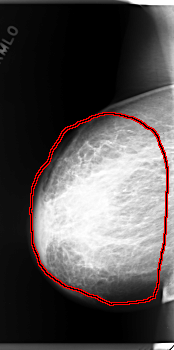

C_0159_1.RIGHT_CC

RIGHT_CC LINES 5944 PIXELS_PER_LINE 2952 BITS_PER_PIXEL 12 RESOLUTION 50 OVERLAY

FILE: C_0159_1.RIGHT_CC.OVERLAY

TOTAL_ABNORMALITIES 1

ABNORMALITY 1

LESION_TYPE MASS SHAPE IRREGULAR MARGINS ILL_DEFINED

ASSESSMENT 5

SUBTLETY 5

PATHOLOGY MALIGNANT

TOTAL_OUTLINES 1

BOUNDARY